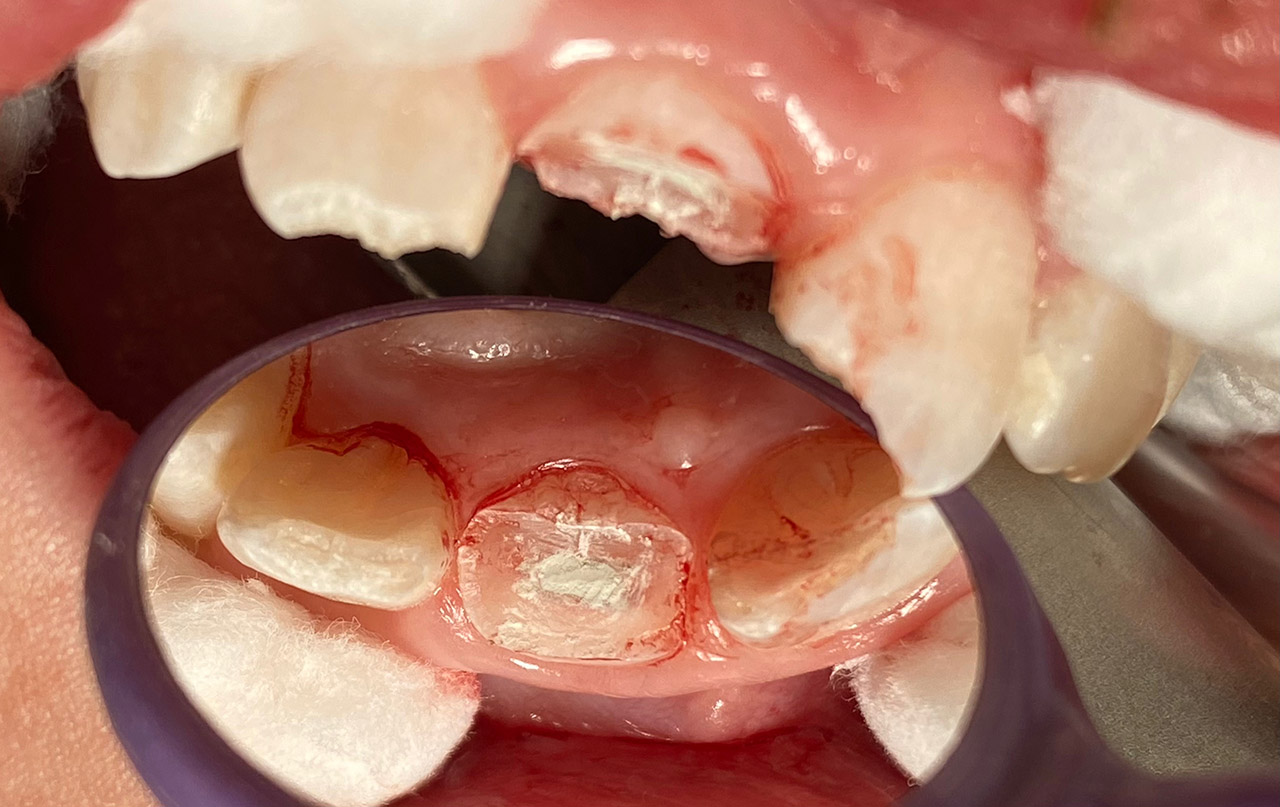

Traumatologie und Endodontie:

Nach Unfall/Sturz mittlerer Schneidezahn auf Gingivaniveau abgebrochen, Pulpa weit eröffnet, beide Nachbarzähne ebenfalls frakturiert.

Erstversorgung: Pulpektomie der Kronenpulpa, MTA, provisorischer Verschluß mit rosa Glasionomerfüllung.

Wiederaufbau der Nachbarzähne mit mitgebrachten (plus 1 Stein) Zahnstücken mit Kunststoff ergänzt und adhäsiv verklebt.

2. Schritt nach Aushärtung von MTA: Entfernung der Kronenpulpa im Bruchstück zur Vermeidung von Verfärbung, Füllung mit Kunststoff.

Adhäsives zementieren des abgebrochenen Zahnstücks.